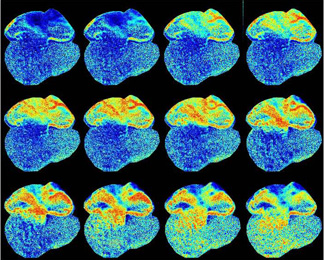

Since the mouse heart beats approximately 6 to 10 times per second, imaging requires a special high-speed camera that is cooled to minus 90 degrees Celsius (minus 128 Fahrenheit), reducing "noise" for a sharper image. Co-author Guy Salama of the University of Pittsburgh contributed the optical imaging work.

Using the new technique, which tracks the rise of calcium as the heart muscle contracts, the researchers discovered a layer of specialized cells on the surface of the developing heart that delays the beating between the upper to lower parts of the heart. After 13.5 days of development, the two portions of the heart separate into four, and there is a functional AV node. By that time, the technique revealed, the specialized cells have died so that functions are not duplicated.